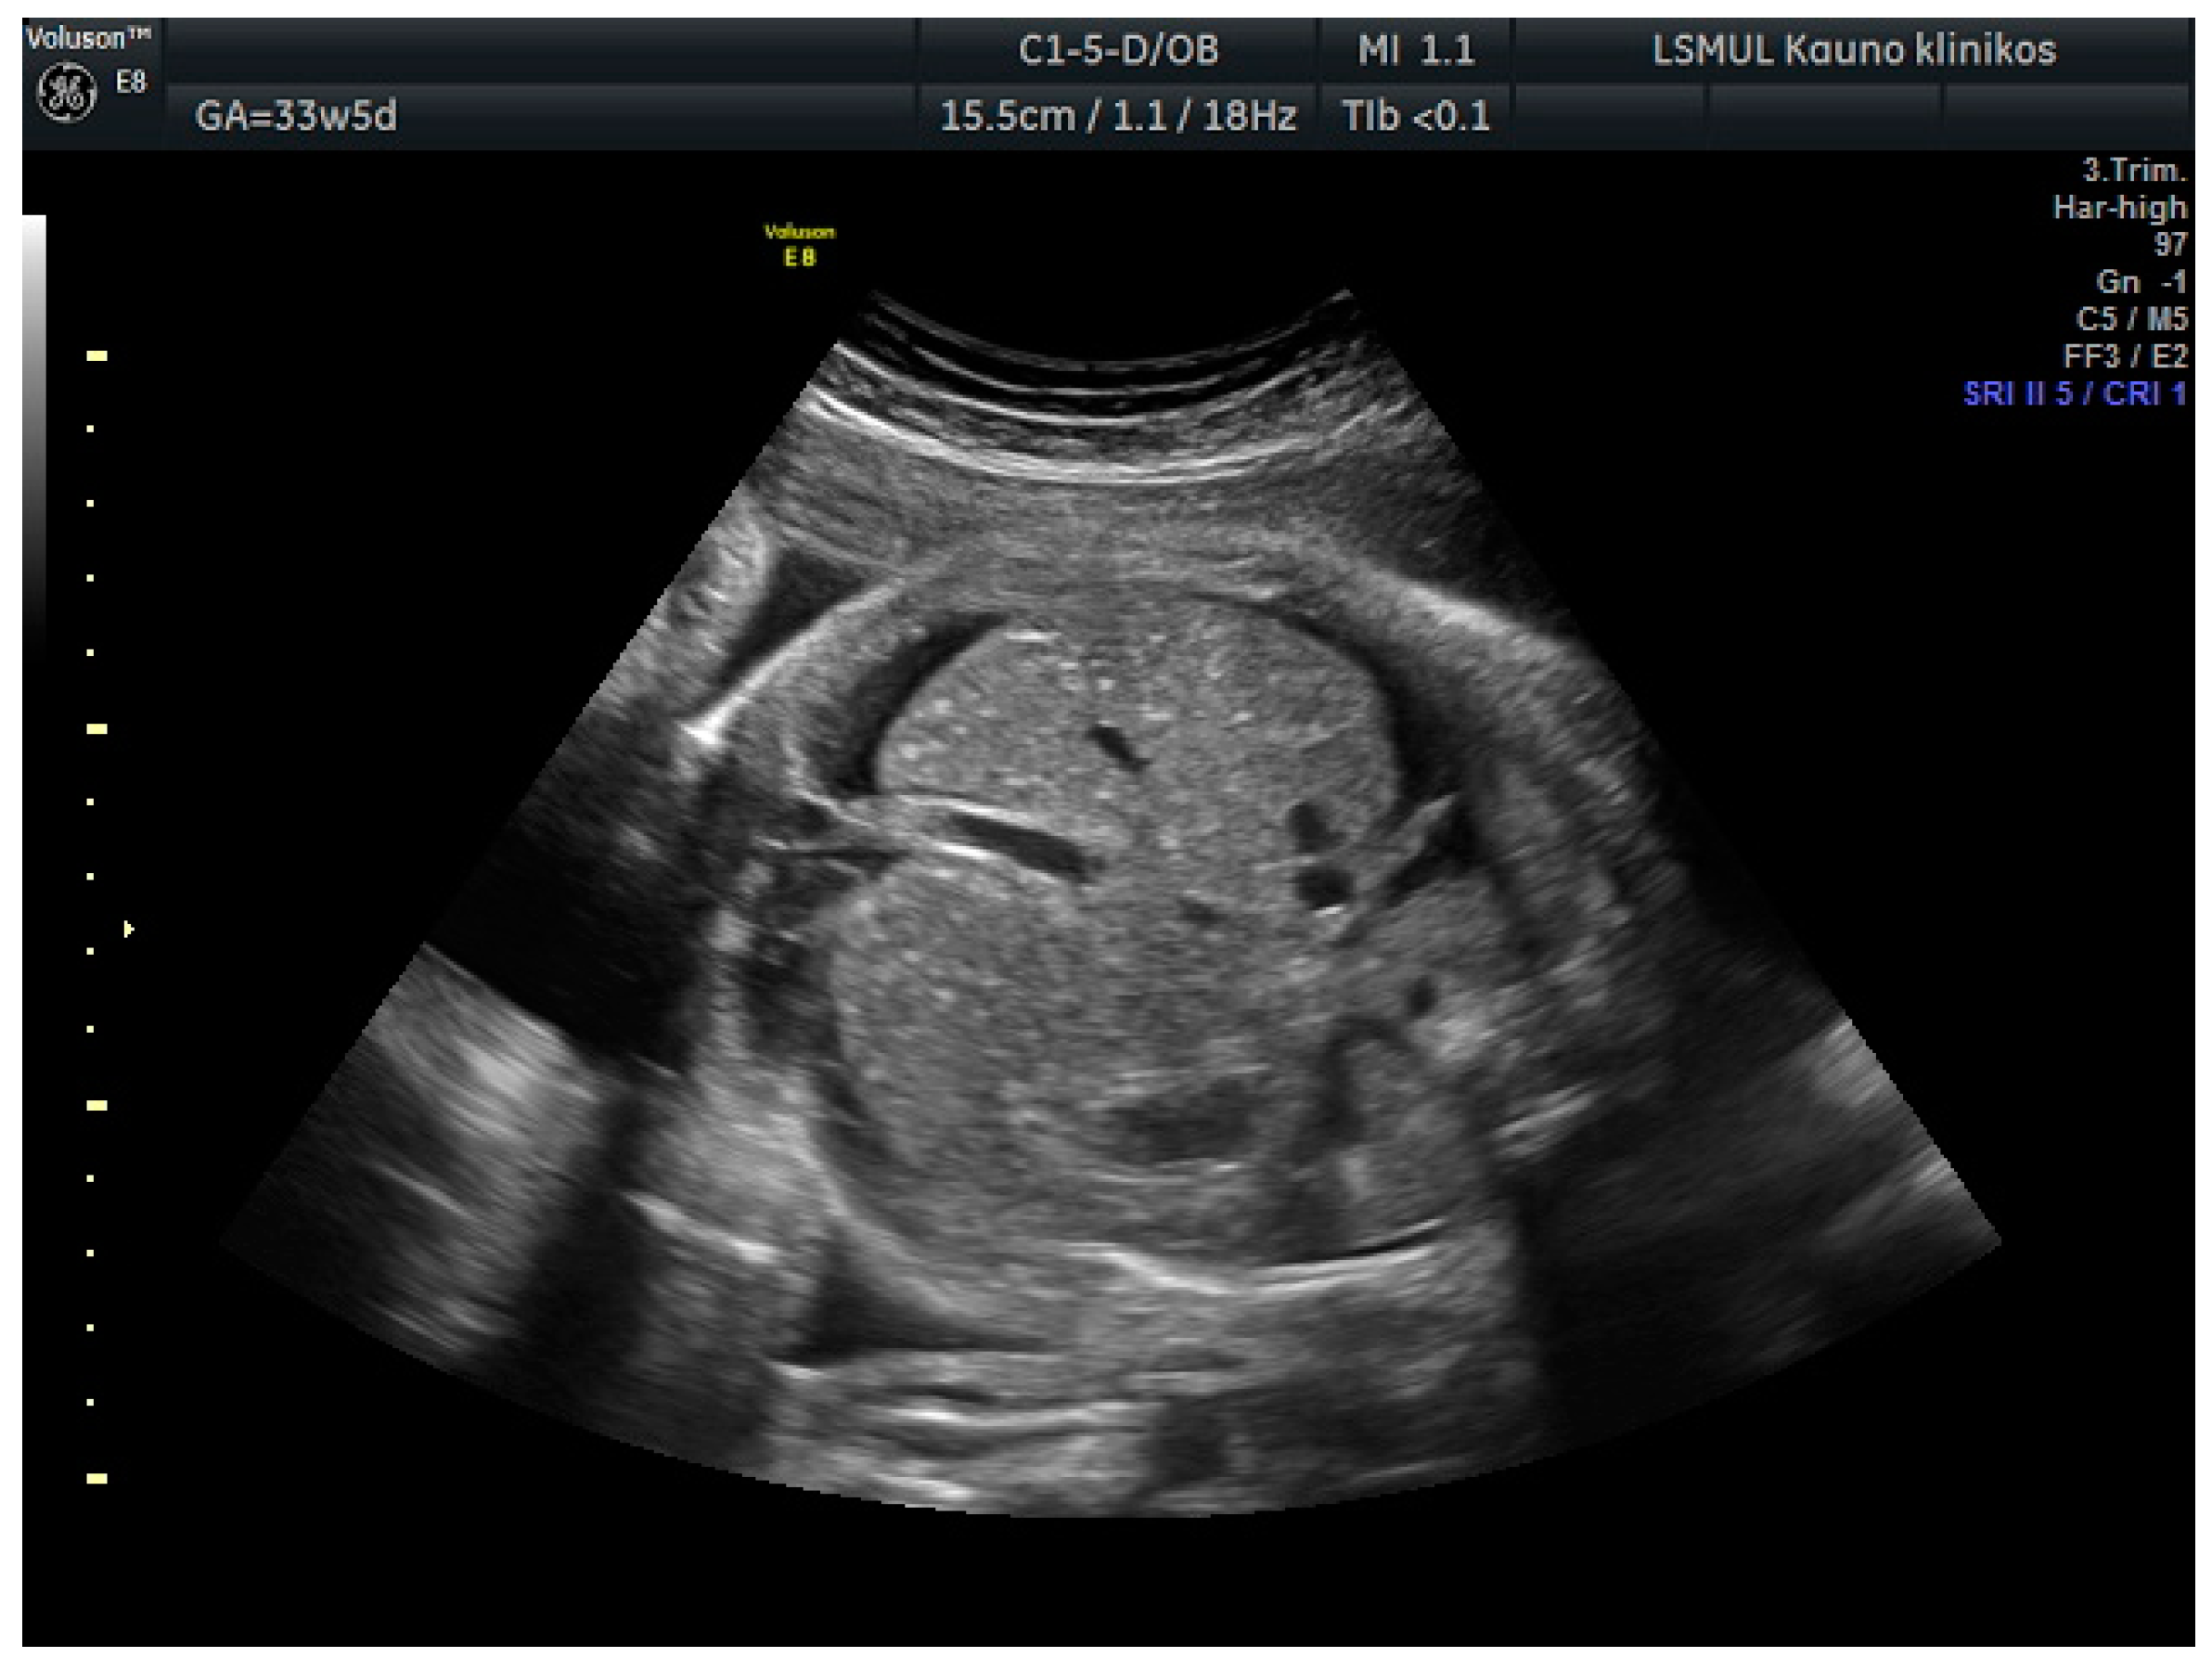

A 34-year-old gravida 3, para 1, aborta 1, noted a loss of fetal motion at 34 weeks of gestation. A two-dimensional ultrasound showed fetal supraventricular tachycardia (fetal heart rate: 284 bpm), signs of fetal hydrops—ascites, pleural and pericardial effusion (Figure 1 and Figure 2). No cardiac or other structural fetal anomalies were found, as well as no anemia—middle cerebral arterypeak systolic velocity was 29 cm/s. We report on a male fetus, biometrical data adequate to gestational age. Electronic fetal heart rate monitoring failed to track the FHR due to its rapidity. The patient had a history of laboratory confirmed influenza at 30 weeks of gestation and was treated with oseltamivir. She gave birth to a healthy boy five years ago.

Figure 2. Ascites.